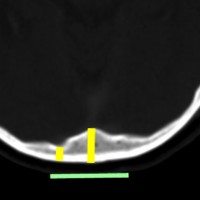

ビデオに見せているように下方から除いて横にドリルを動かしながら削除するのが効率的です。正中は内後頭隆起のためにとても深く厚い骨削除(黄色の線)となります。しかし,左右外側方向は後頭葉後頭極がありますので頭蓋骨が相対的に薄く硬膜がすぐにでます。両側の後頭極硬膜を確認しておいてから,内後頭隆起の深い骨稜を削除することが安全です。後頭極を覆う頭蓋骨の厚さには個人差があり,とても薄い骨の人がいますので気をつけます。緑の線の幅くらいを横に広く開けます。

もし,このように矢状洞が左に寄っているタイプであれば,右後頭開頭をして,右の後頭極を牽引して,大脳半球間裂の右側から入った方が有利です。理解しやすいように左右反転していますので,MRIは左右逆でみてください。